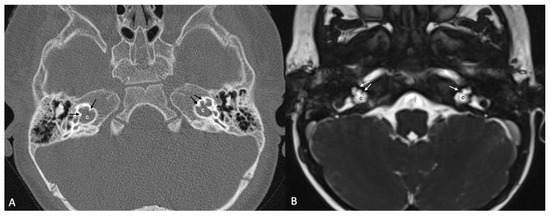

One patient exhibited IP-1 in the right ear and LA in the left ear. The right vestibule was hypoplastic, and the SCCs appeared as a single bud. The diameters of the right IAC and cochlear nerve were within normal limits. However, the stapes, oval and round windows, cochlea, vestibule, SCCs, IAC, and vestibulocochlear nerve could not be detected in the left ear. Cochlear implantation was performed in the right ear of this patient (Figure 3). Bilateral IP-3 anomalies were detected in two siblings. In these cases, the oval and round windows were also malformed. While both cochlear nerves of one sibling exhibited hypoplasia, the cochlear nerves of the other sibling were within normal limits as they were thicker than the facial nerves (Figure 4).

Figure 4.

(A) CT and (B) MRI images of a case of bilateral IP-3 (incomplete partition type-3). Note that despite the relative preservation of the outer contour of both cochleae (c) and the presence of interscalar septae (black and white arrows), the inner structure is featureless and the modiolus is absent.